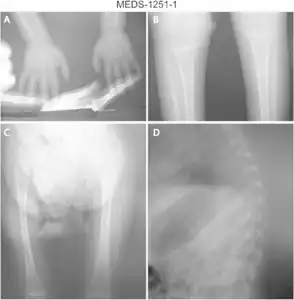

Diagnostic methodBone density scan

DXA scanners can be used to diagnose osteopenia or osteoporosis as well as to measure bone density over time as people age or undergo medical treatment or lifestyle changes.[18]

Information from the DXA scanner creates a bone mineral density T-score by comparing a patient's density to the bone density of a healthy young person. Bone density between 1 and 2.5 standard deviations below the reference, or a T-score between −1.0 and −2.5, indicates osteopenia (a T-score smaller than or equal to −2.5 indicates osteoporosis). Calculation of the T-score itself may not be standardized. The ISCD recommends using Caucasian women between 20 and 29 years old as the baseline for bone density for ALL patients, but not all facilities follow this recommendation.[19][20][21][22]

The ISCD (International Society for Clinical Densitometry) and the National Osteoporosis Foundation recommend that older adults (women over 65 and men over 70) and adults with risk factors for low bone mass, or previous fragility fractures, undergo DXA testing.[22] The DXA (dual X-ray absorptiometry) scan uses a form of X-ray technology, and offers accurate bone mineral density results with low radiation exposure.[24][25]

The United States Preventive Task Force recommends osteoporosis screening for women with increased risk over 65 and states there is insufficient evidence to support screening men.[26] The main purpose of screening is to prevent fractures. Of note, USPSTF screening guidelines are for osteoporosis, not specifically osteopenia. The National Osteoporosis Foundation recommends use of central (hip and spine) DXA testing for accurate measure of bone density, emphasizing that peripheral or "screening" scanners should not be used to make clinically meaningful diagnoses and that peripheral and central DXA scans cannot be compared to each other.[27]